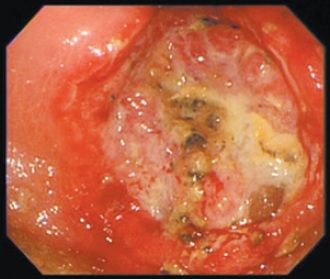

圖1:胃腺癌造成的胃潰瘍

胃鏡檢查是最容易且能快速診斷有無胃癌的方法,在胃鏡檢查中如果發現不易癒合或易出血的潰瘍(圖1、圖2),可經由病理切片來判斷為惡性或良性。某些不適合做胃鏡的患者,例如食道狹窄、意識不清無法配合、嚴重心律不整、懷疑腸穿孔等,則可選擇以上消化道攝影、腹部電腦斷層等檢查方式來取代胃鏡。